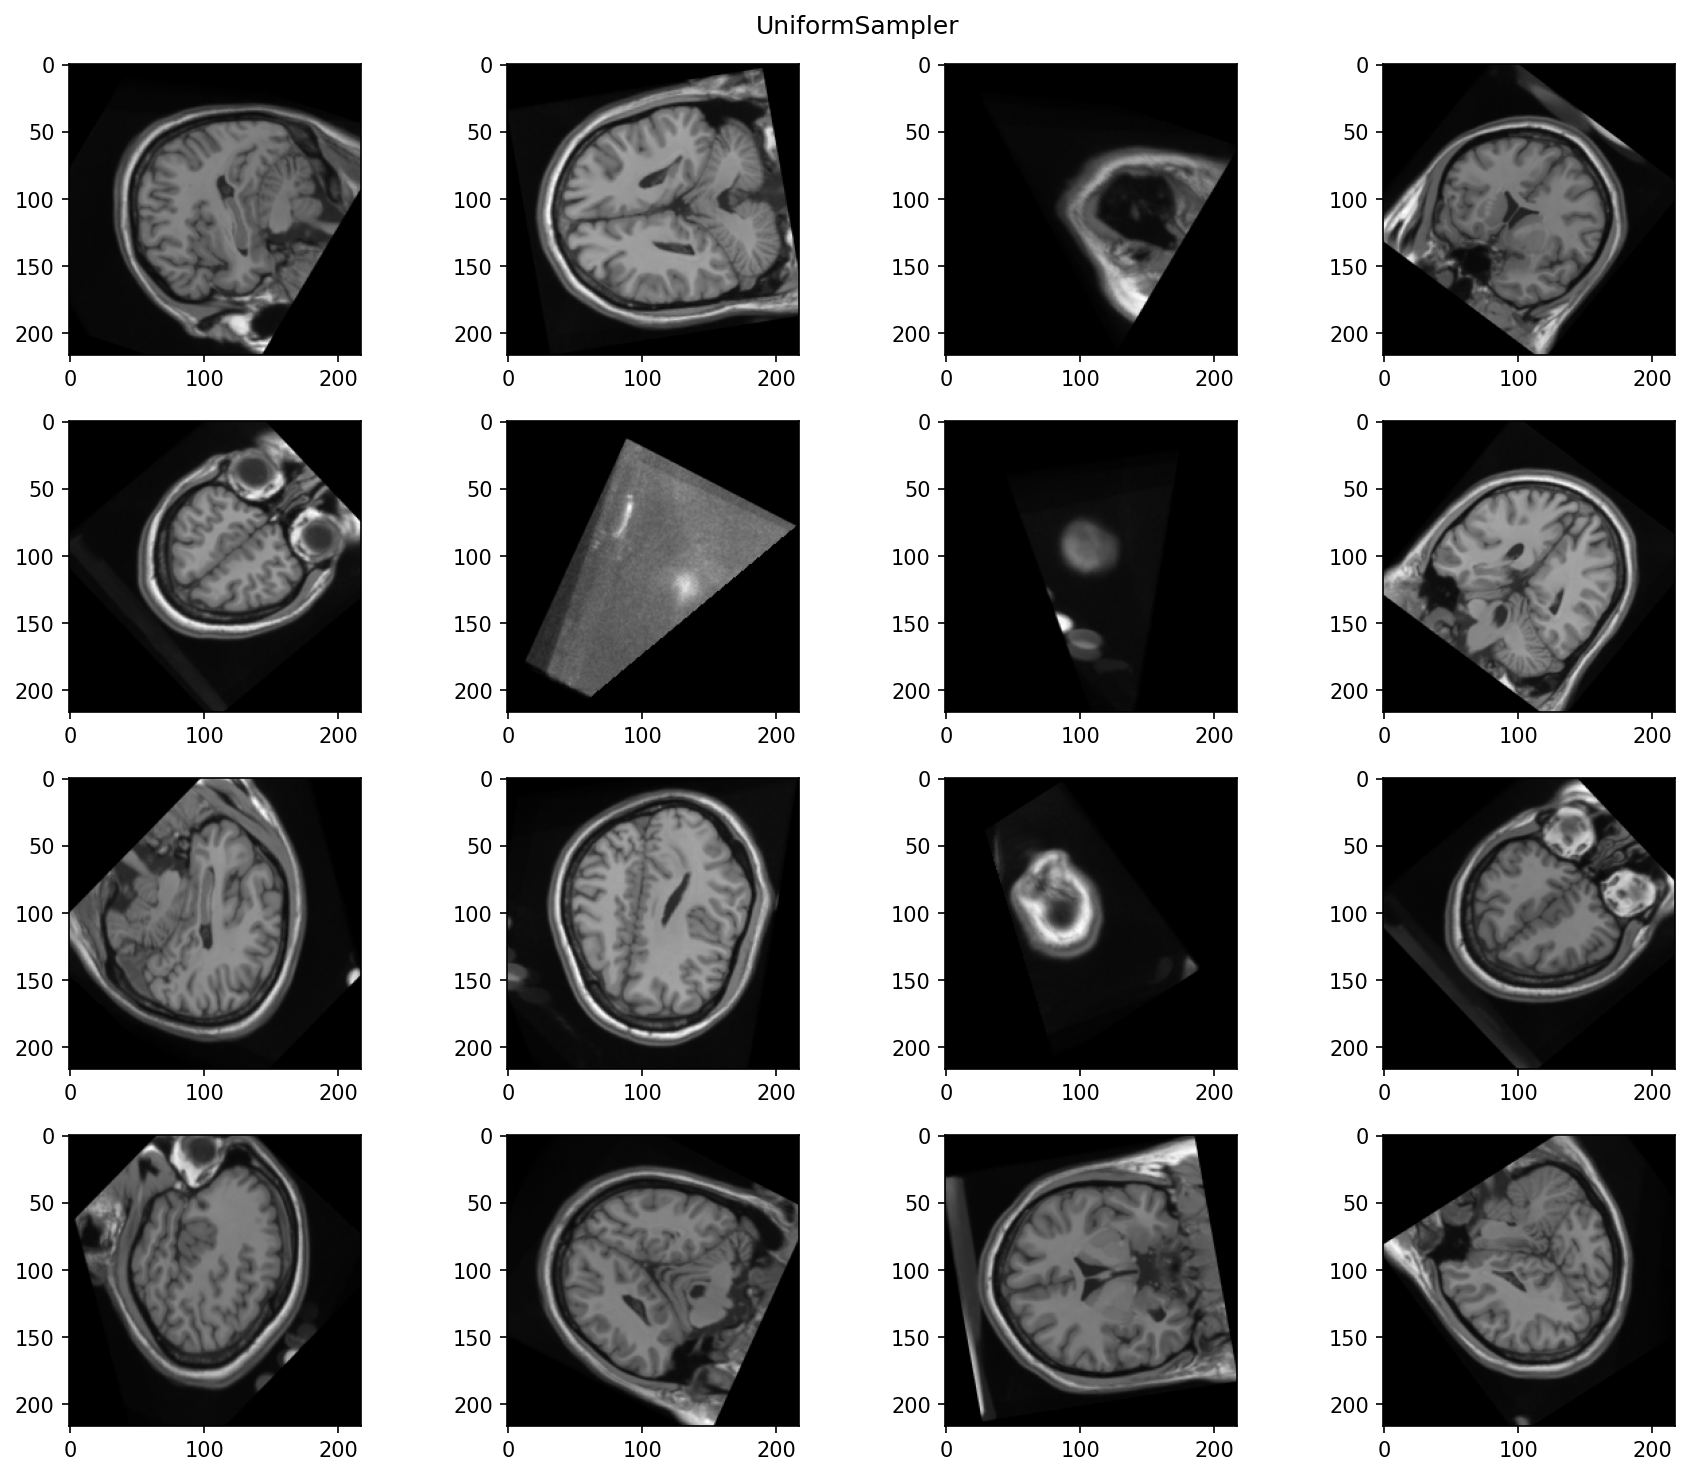

Uniform sampler

When a torchio.UniformSampler is used,

some of the patches don't contain much useful information: